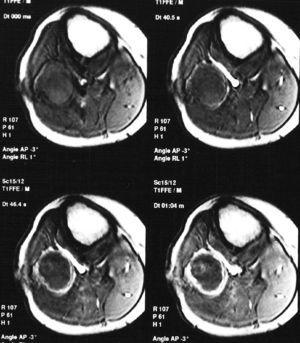

Paciente varón de 15 años, que fue remitido a consultas de traumatología por genu valgo. No tenía antecedentes de interés, salvo crisis asmáticas en la infancia, y la presencia de una lesión lítica ya conocida en el peroné, que sugería el diagnóstico diferencial de displasia fibrosa o quiste óseo aneurismático como primeras posibilidades. La lesión parecía haber crecido respecto a estudios previos. En la radiografía simple (fig. 3), se identificaba una gran lesión lítica expansiva que afectaba predominantemente a la metáfisis proximal del peroné derecho, extendiéndose caudalmente a la diáfisis, y limitada superiormente por la placa de crecimiento. No tenía matriz ósea interna y la zona de transición, al menos en la zona inferior, era estrecha. En el interior presentaba un patrón de múltiples septos con cierto adelgazamiento endostal. En la TC (fig. 4) la cortical estaba muy adelgazada, con focos de discontinuidad sin identificar masa de partes blandas, y presentaba finos septos internos. Se realizó un estudio mediante RM con un equipo de 1,5T (Gyroscan Philips Intera). En la RM el tamaño aproximado de la lesión era de 8,5 x 3,3 x 3 cm (craneocaudal x anteroposterior x lateromedial). La lesión insuflaba el peroné sin visualizar masa de partes blandas. En la secuencia T1-ES (TR/TE 460/15) se comportaba hipointensa de forma homogénea (fig. 5). En la secuencia STIR (1688/15) (fig. 6) parecía tener dos componentes, con diferentes intensidades de señal. El superior hipointenso y el inferior levemente hiperintenso. En la secuencia dinámica T1 (TR/ TE 460/15) tras gadolinio itravenoso (figs. 7 y 8) presentaba un leve realce periférico del componente superior en fase tardía con prácticamente nulo realce en fase precoz y, sin embargo, un intenso realce del componente inferior en fase precoz, seis segundos después de que el contraste se identificase en el interior de los vasos arteriales, con realce persistente en fase tardía (fig. 9). Se realizó una gammagrafía ósea de cuerpo completo en proyecciones anterior y posterior en tres fases. En la fase vascular se observaba un incremento en la llegada del radiotrazador del pool sanguíneo a la región proximal del peroné derecho. La imagen tardía mostraba una hipercaptación en el extremo proximal de dicho hueso. Descartaba la posibilidad de quiste óseo, que no suelen mostrar captación en la gammagrafía y aconsejaban descartar otro tipo de tumoración ósea. No se visualizaron otras lesiones a distancia. En estos momentos el diagnóstico diferencial propuesto fue de fibroma condromixoide, fibroma desmoplásico y quiste óseo aneurismático, a pesar de la ausencia de niveles líquido-líquido. A continuación se realizó una biopsia abierta, con diagnóstico de fibroma desmoplásico. En el estudio macroscópico se identificaban varios fragmentos blanquecinos de consistencia ósea. En el estudio microscópico, se identificó una proliferación de células elongadas, separadas de abundantes fibras de colágeno. La densidad celular era muy variable en función del campo estudiado, lo mismo que la disposición de las fibras de colágeno, bien onduladas o con gran laxitud. Las células tenían núcleos ovoideos, sin aparentes nucleolos y sin figuras mitóticas. Algunos de los remanentes óseos atrapados en la muestra tenían actividad osteoclástica, sin ver en ningún momento atipias.

Fig. 5.--Secuencia coronal T1-ES. La lesión aparece homogéneamente hipointensa, de comportamiento expansivo, limitada superiormente por la phisis.

Fig. 6.--Secuencia STIR coronal. Se diferencian los dos componentes. El superior hipointenso con una halo de hiperseñal y el inferior hiperintenso sin asociarse a masa de partes blandas.

La RM permite una clara delimitación entre el hueso normal y el tumoral. Generalmente aparece hipointenso tanto en las secuencias T1 como T2, como los linfomas o los tumores fibrosos, debido a la densa matriz conectiva, y para algunos autores debido a la relativa hipocelularidad, lo que significa una disminución de los protones móviles6. Otros autores recogen otros hallazgos, como la presencia de una pseudocápsula, focos de necrosis, niveles líquido-líquido dentro del tumor8 y, en ocasiones, un comportamiento hiperintenso en las secuencias T22,4. En nuestro caso se identificaban dos componentes diferentes dentro de la misma lesión de diferente señal en las secuencias T2. El componente superior es hipointenso y el inferior de intensidad intermedia. En las secuencias dinámicas postgadolinio intravenoso, el componente superior mostraba un leve realce periférico en fase tardía con prácticamente nulo realce en fase precoz y el componente inferior presentaba intenso realce en fase precoz, que persistía en fases tardías.